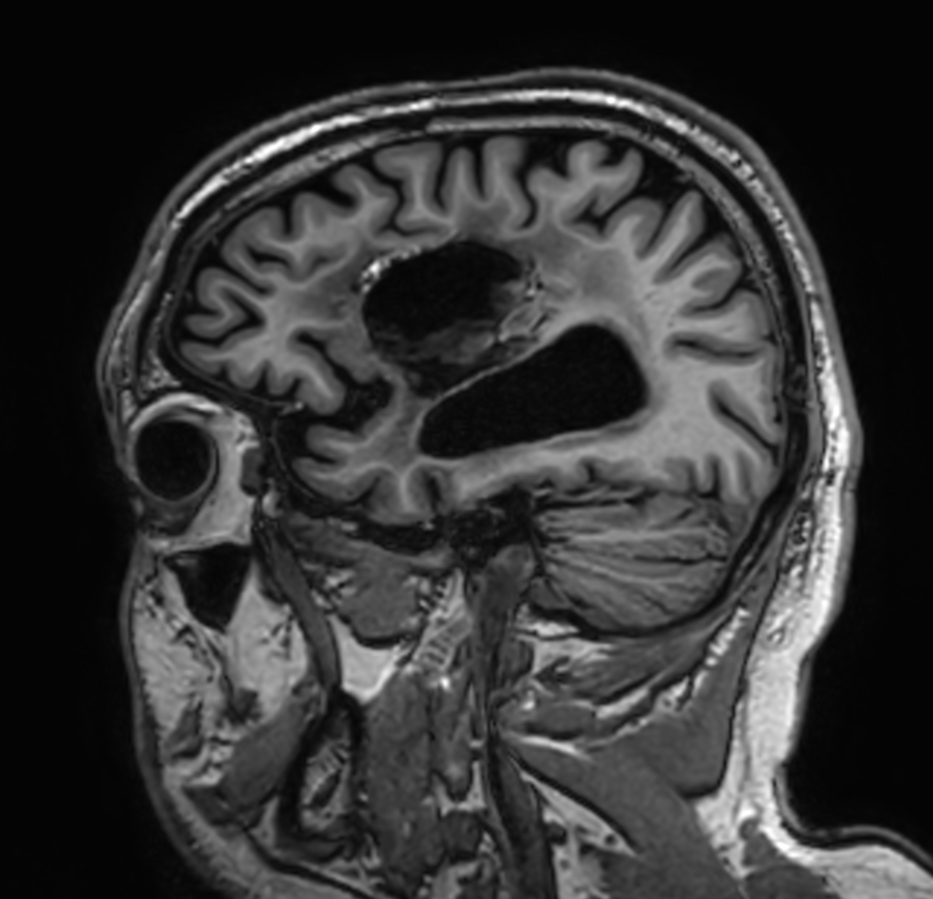

Brain glioblastoma, post-operative

Patient who was operated on glioblastoma

Sagittal 3D T1w TFE